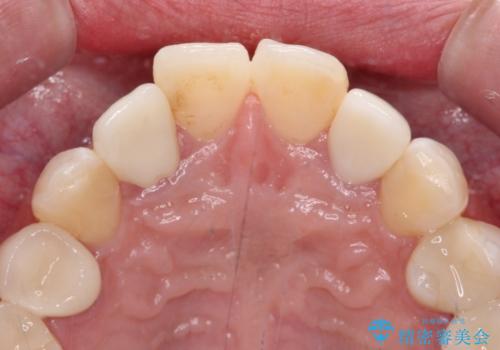

- クラウンから金属の土台が見えてきてしまったとのことで、作り替えを希望して来院された患者様です。

前歯や金属が露出している歯、痛みを感じる歯を中心に、オールセラミッククラウンにて補綴治療することとしました。

以前はセラミッククラウンのフレームとして金属が使用されており、歯肉の経年変化やセラミックのすり減りなどにより、金属が見えるようになってくることがあります。

現在は金属の代わりに強化セラミックを使用したオールセラミッククラウンが主流です。金属色が気になる方はご相談ください。